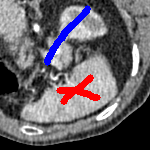

We now introduce two recent methods that incorporate user input to perform selective segmentation. Each involves input in the form of foreground/background regions to indicate relevant structures of interest. An example of this can be seen in Fig. 18, where red regions indicate foreground and blue regions indicate background. We compare against the work of Nguyen et al. Nguyen:12 , which uses a similar convex relaxation framework to the proposed approach, and Dong et al. SRW , which uses a variation of the random walk approach. We summarise the essential aspects of each approach in the following.

In order to further establish the robustness of our method, we now introduce the results of testing our approach against competing interactive segmentation methods on a larger data set. The results are presented in Fig. 17, showing a boxplot of accuracy in terms of TC on a set of 30 CT images (excluding outliers). The target structure we consider is the spleen, as this consists of a relatively homogeneous foreground, appropriate for the approach considered. The data has been manually contoured providing ground truth data for the image set. We compare CAC Nguyen:12 and SRW SRW against our method with five variations of user input for each image. It is worth emphasising here that the input used in the tests is identical for each approach and was not refined in any way. It was designed to mimic what a user, unfamiliar with each approach, might select intuitively. A representative example for three images is shown in Fig. 18. This shows foreground (red) and background (blue) user input regions. For our method, we define the red region as as discussed in §1 and enforce hard constraints on the blue region. We refer to the results of the proposed approach using this input as Ours (i). We also include results of randomising the user input in an identical way to §7.3. For each image we generate 1000 simulated user input choices, which we present as Ours (ii). It is important to note that the difference between Ours (i) and (ii) is only the definition of . The method and parameters are fixed between each.